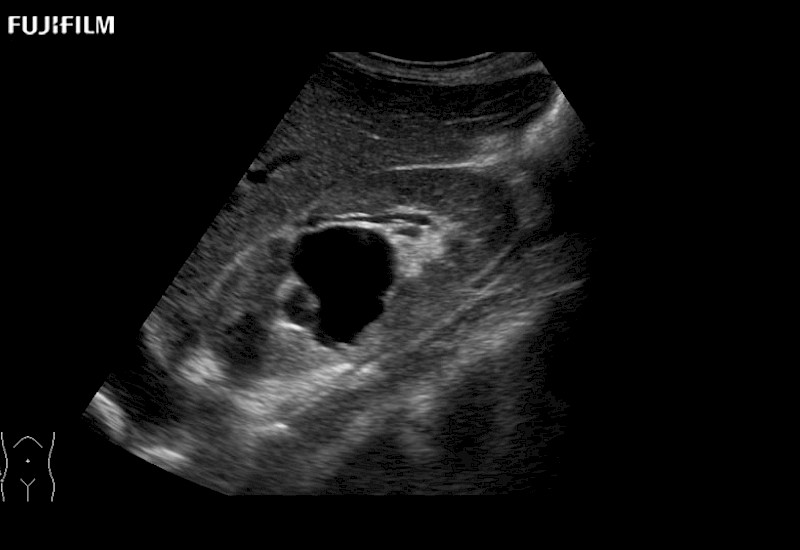

Fujifilm Healthcare understands that Surgical Oncologists demand excellence in their operating rooms — from their staff and the equipment they depend on. Fujifilm Healthcare's dedication to Surgical Oncologists provides outstanding ultrasound technology, professional support and the specialized tools necessary to best perform comprehensive real-time ultrasound imaging.

For precise surgical oncology ultrasound imaging, Fujifilm Healthcare offers premium level solutions that include:

for use during open and laparoscopic procedures: Tumor localization & staging, Ablation, Resection, Biopsy, Transplant, Abdominal exploration, Robotic surgery

Our dedication to Surgical Oncology allows us to offer superior image quality, outstanding system reliability and intuitive use of cutting edge technology.